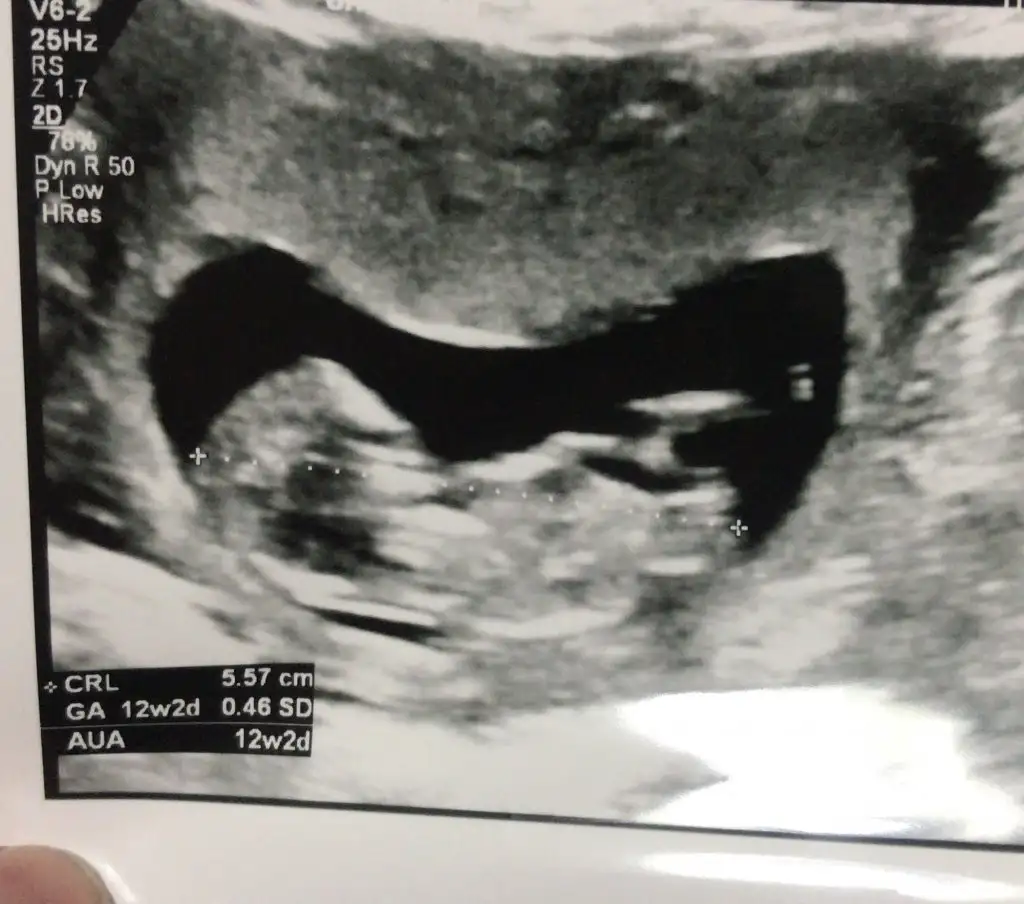

Merhaba bu fotoğrafı da yorumlayabilir misiniz?😊 12+3 haftalık doktor henüz çok erken dedi. 2 hafta sonra gel dedi ama araya bayram tatili giriyor ondan sonra da şehir dışına çıkmam gerekiyor.haliyle çok merak ediyorum.@Ikra meyra

Erkek gibi sanki